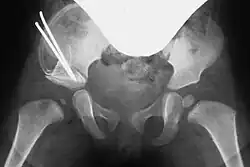

Acetabuloplasty, Step 4: Optional fixation with a Kirschner wire

In both techniques, a suitably shaped bone wedge is inserted into the resulting gap under X-ray guidance. If needed, the wedge can be fixed with an osteosynthesis wire (Kirschner wire). The procedure typically takes 45 to 60 minutes for an experienced surgeon.[3][11]

Post-surgery, a pelvic spica cast (modified Fettweiss cast) or abduction orthosis is applied to keep the femoral head centered in the acetabulum during healing. Anesthesia is discontinued afterward.[7]